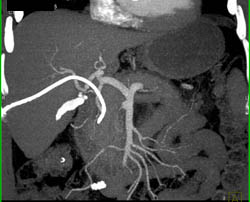

Cholangiocarcinoma